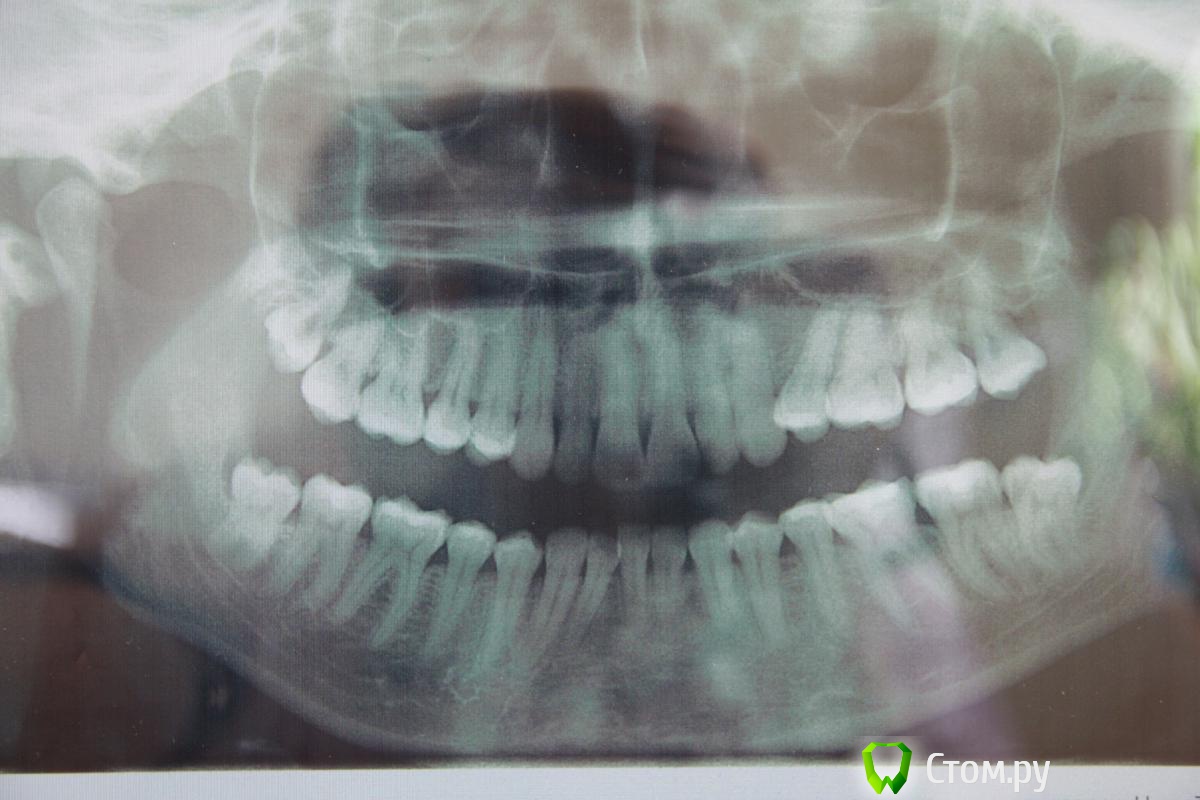

Цунами Опубликовано 16 апреля, 2014 Автор Поделиться Опубликовано 16 апреля, 2014 (изменено) Добрый день.Сегодня сделала снимок (снимок не распечатывали на плёнке, прислали на почту, надеюсь, качество снимка хорошее?)Всё ли хорошо на снимке. Какая-то полосочка видна ближе к семёрке? Может это нитки видны?Удаление зуба было в пятницу 11 апреля. В понедельник ходила на осмотр - убрали резиночку-дренаж. Изменено 16 апреля, 2014 пользователем Цунами Ссылка на комментарий

Цунами Опубликовано 16 апреля, 2014 Автор Поделиться Опубликовано 16 апреля, 2014 Смотрю, в соседней теме "Какова цена такого зуба" врачи активно отвечают. Может быть и мне ответите, я заплатила за удаление зуба восемь тысяч. Это нормальная цена?Скажите пожалуйста, лунка на снимке хорошо выглядит? Ссылка на комментарий

red_butler Опубликовано 16 апреля, 2014 Поделиться Опубликовано 16 апреля, 2014 Добрый день.Сегодня сделала снимок (снимок не распечатывали на плёнке, прислали на почту, надеюсь, качество снимка хорошее?)Всё ли хорошо на снимке.Все хорошо Ссылка на комментарий

IvanK Опубликовано 17 апреля, 2014 Поделиться Опубликовано 17 апреля, 2014 Все хорошо+1 Ссылка на комментарий